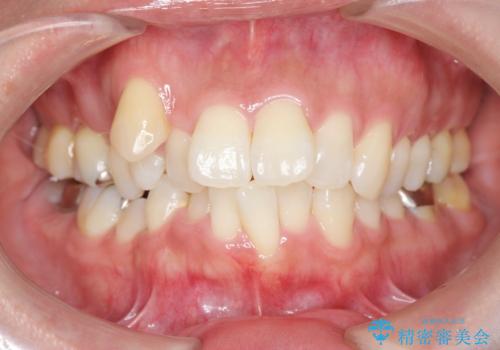

職業柄ワイヤー矯正ができない、マウスピース矯正で行う八重歯抜歯症例

- 「長年気になっている八重歯を矯正治療で治したい、ただし職業柄ワイヤー矯正は絶対にできないのでマウスピース矯正を希望。」

、と矯正治療を希望され来院されました。

通常は八重歯の抜去は行わず、小臼歯の抜去を行いワイヤー矯正を行いますが、八重歯を抜去することでマウスピースで現実的に達成できる機能的な歯並びを獲得できるよう治療計画を立案します。